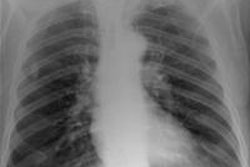

They tested the model in a "virtual clinical trial" in which four experienced image evaluators graded images of average and obese adult patients at different potentials, receptor doses, and scatter rejection techniques on an Agfa HealthCare CR system using MD-4.0 phosphor plates. The quality of the images was evaluated using visually graded analysis. The researchers also assessed the influence of rib contrast.

Simulated chest images of an average-sized patient reconstructed at 50 kVp (a) and 150 kVp (b). Image (a) is of higher contrast, which is expected. All images courtesy of Craig Moore.For average-sized patients, image quality improved when tube potential was reduced compared with the reference (102 kVp) and no scatter rejection was indicated. For obese patients, it has been shown that an antiscatter grid is indicated and should be used in conjunction with as low a tube potential as possible (while allowing exposure times, 20 msec), the researchers wrote. It is also possible to reduce receptor air kerma by 50% without adversely influencing image quality. They also found rib contrast did not interfere at any tube potential.